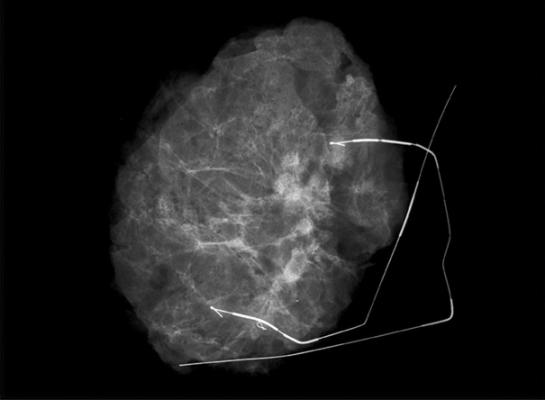

October 4, 2017 — Kubtec announced at the annual conference of the American Association of Pathology Assistants (AAPA) that they are expanding their proprietary use of 3-D tomosynthesis by bringing it to the XPERT 80 Specimen X-ray System. Kubtec introduced 3-D imaging for clinical specimens with the Mozart System, the first specimen X-ray system to use 3-D tomosynthesis, according to the company.

This technology has now been scaled up to enable healthcare professionals to visualize larger specimens such as full mastectomies and even the longest of bone specimens — all in 3-D.